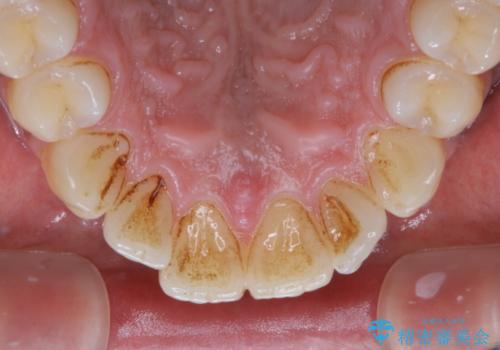

他人から口臭を指摘されて初めてのPMTC

- 他人から口臭を指摘されたので歯のクリーニング希望との事でした。

PMTC60分コースを行いました。

PMTCとはProfessinnal Mechanical Tooth Cleaning・専門器具による歯の機械的な清掃です。

バイオフィルム(細菌の塊)を破壊し、歯の表面をツルツルにすることでお口の中の細菌数を減らし歯周病のリスクが定着するのを防ぎます。更に、歯に新しい汚れがつきにくい状態になります。

歯石除去をすることにより、歯と歯の間に隙間が見られることがあります。

ただし、それは今まで歯石により埋め尽されていた状態だったため、開いた隙間は正常な歯肉の状態です。

PMTCを行うことにより、虫歯・歯周病・口臭予防だけでなくスッキリと爽快感が得られたり、見た目も清潔感のある状態になるため、今後の治療などお口に対するモチベーションUPにも繋がります。